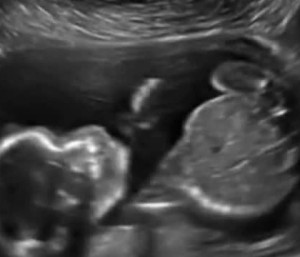

Orice mămică abia așteaptă ecografia de sarcină pentru a-i observa progresele bebelușului. Însă, mare îți este surprinderea atunci când vezi ceva ce alții nu prea au mai întâlnit – bebelușul se bate singur în pântecul mamei.

O gravidă din Kansas a fost cu adevărat cutremurată atunci când în timpul efectuării ecografiei de sarcină și-a surprins bebelușul cum își dădea singur un pumn. Cu siguranță, ar fi vrut să vadă cu totul altceva, drept pentru care o astfel de imagine a creat o stare de neliniște, de teamă ca bebelușul să nu pățească ceva.

Medicul a asigurat-o că Edward James Watson, bebelușul ce urma să se nască, nu a pățit uimit. Desigur, la fel de surprins a fost și obstreticianul care nu mai văzuse așa ceva în cei 20 de ani de când practica meseria.